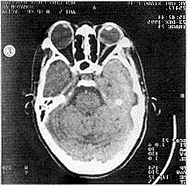

眼與眼眶:CT可直接顯示眶內軟組織結構和病變,同時提供眼部及其周圍的活體解剖層面圖像,清楚顯示眼球、視神經和眼外肌,有利於肌錐內、外的區域劃分和象限定位。CT可同時顯示軟組織和骨結構,發現細小鈣化和骨質改變,是優於MRI的突出特點。CT能確定眶內腫瘤的存在、位置、大小及範圍,並可對良性和惡性進行鑑別。良性腫瘤呈邊緣清楚、光滑,密度均勻的高密度腫塊;惡性腫瘤形態不規則,邊界不清,密度不均,常有眶骨破壞,並向顱內、鼻竇蔓延。眼球腫瘤累及脈絡膜,表現為眼環偏心性肥厚,並突向眼環內,也可向球後延伸進進球後間隙。增強掃描有助於腫瘤的定性診斷,對海綿狀血管瘤的診斷有特殊意義。